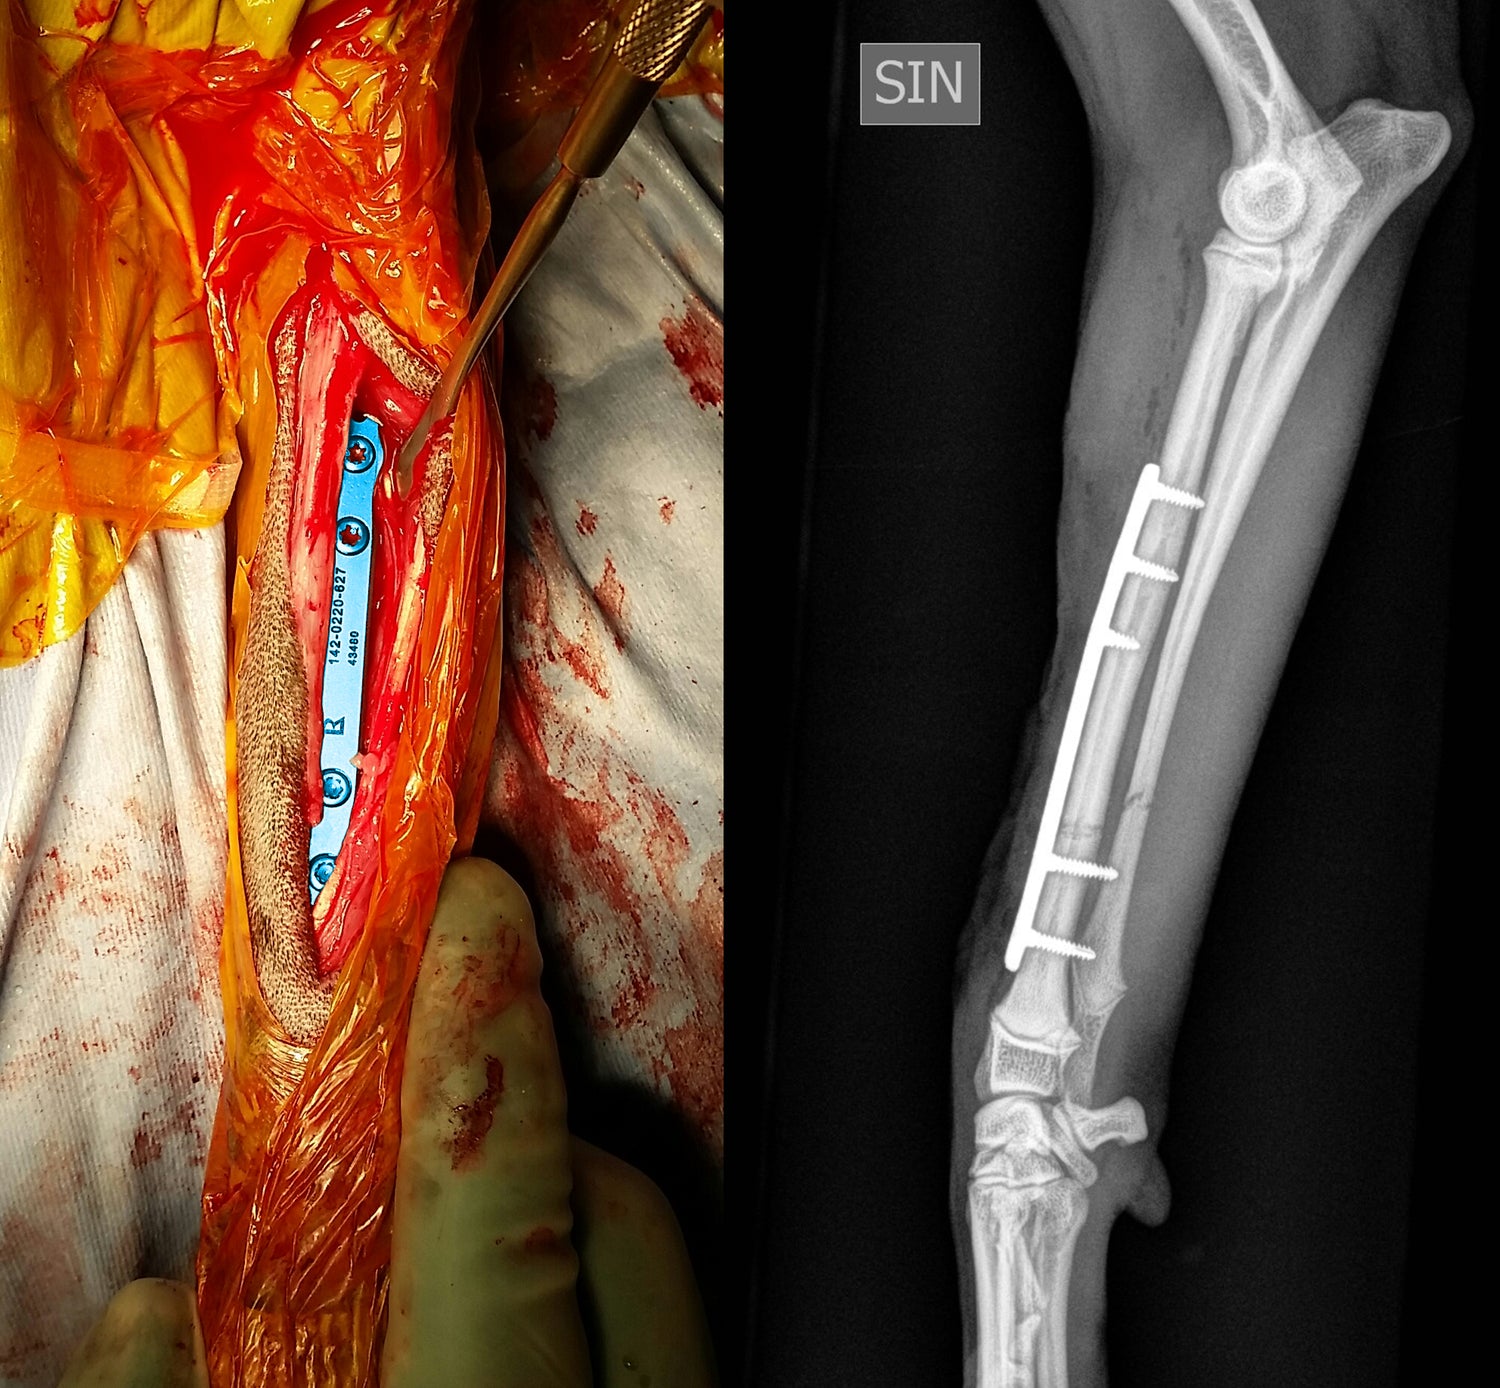

This course is designed for small animal practitioners seeking practical, effective methods to manage long bone fractures in dogs and cats. Participants will learn simplified techniques suitable for both straightforward and comminuted fractures, using modern implants that enhance surgical efficiency and reduce costs. By following key principles of fracture repair, complications can be minimized and outcomes improved.

Through a combination of lectures, clinical case discussions, and hands-on practice, attendees will gain confidence in choosing appropriate fixation methods and performing repairs. Practical sessions include fracture repair on plastic bone models and cadavers, followed by postoperative radiographs to assess technique and reinforce learning.

Learn direct and indirect fracture reduction techniques and when to apply each approach

Apply the biomechanics of intramedullary pins, cerclage wires, bone screws, and plates, including compression, neutralization, and bridging methods